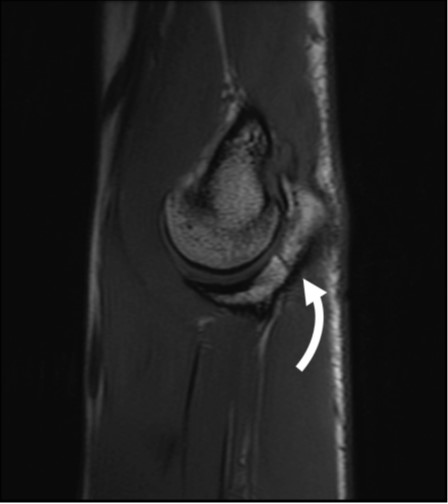

Pseudodefect of the Trochlear Groove

The trochlear groove is constricted at the junction of the olecranon and coracoid process with inward tapering that results in subtle cortical notches peripherally, which can simulate cortical disruption on sagittal MR images. These pseudodefects of the trochlear groove can simulate a fracture (Fig. 4). However, the well-defined margins, absence of bone marrow edema, and midtrochlear location differentiate the pseudodefect from a true fracture, which usually extends into the medullary cavity [1, 2, 13].